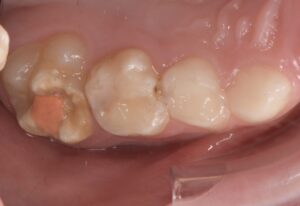

Le congrès de l’EAPD (Académie Européenne d’Odontologie Pédiatrique) a défini des critères de diagnostic en 2003. A savoir des opacités délimités, des fractures post-éruptives, des restaurations atypiques ainsi que que des extractions des molaires. (3) Le diagnostic différentiel doit surtout s’établir entre des amélogénèses imparfaites et des hypominéralisations d’origine traumatique pour les dents antérieures. Cliniquement, les dents vont présenter des colorations blanches ou brunes opaques sur une partie ou sur toute la surface de la dent (Figures 1-2-3-4).

formation dentaire pédodontie Figure 3.

Figure 3-4 : Molaires atteintes de MIH (HSPM + MIH pour la figure 3)